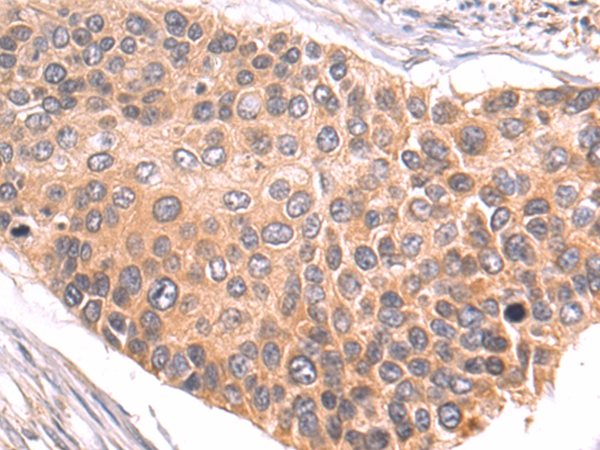

分类: 科研抗体货号: P07433别名: NRAGE, DLXIN-1应用: WB,IHC反应种属: Human, Mouse, Rat